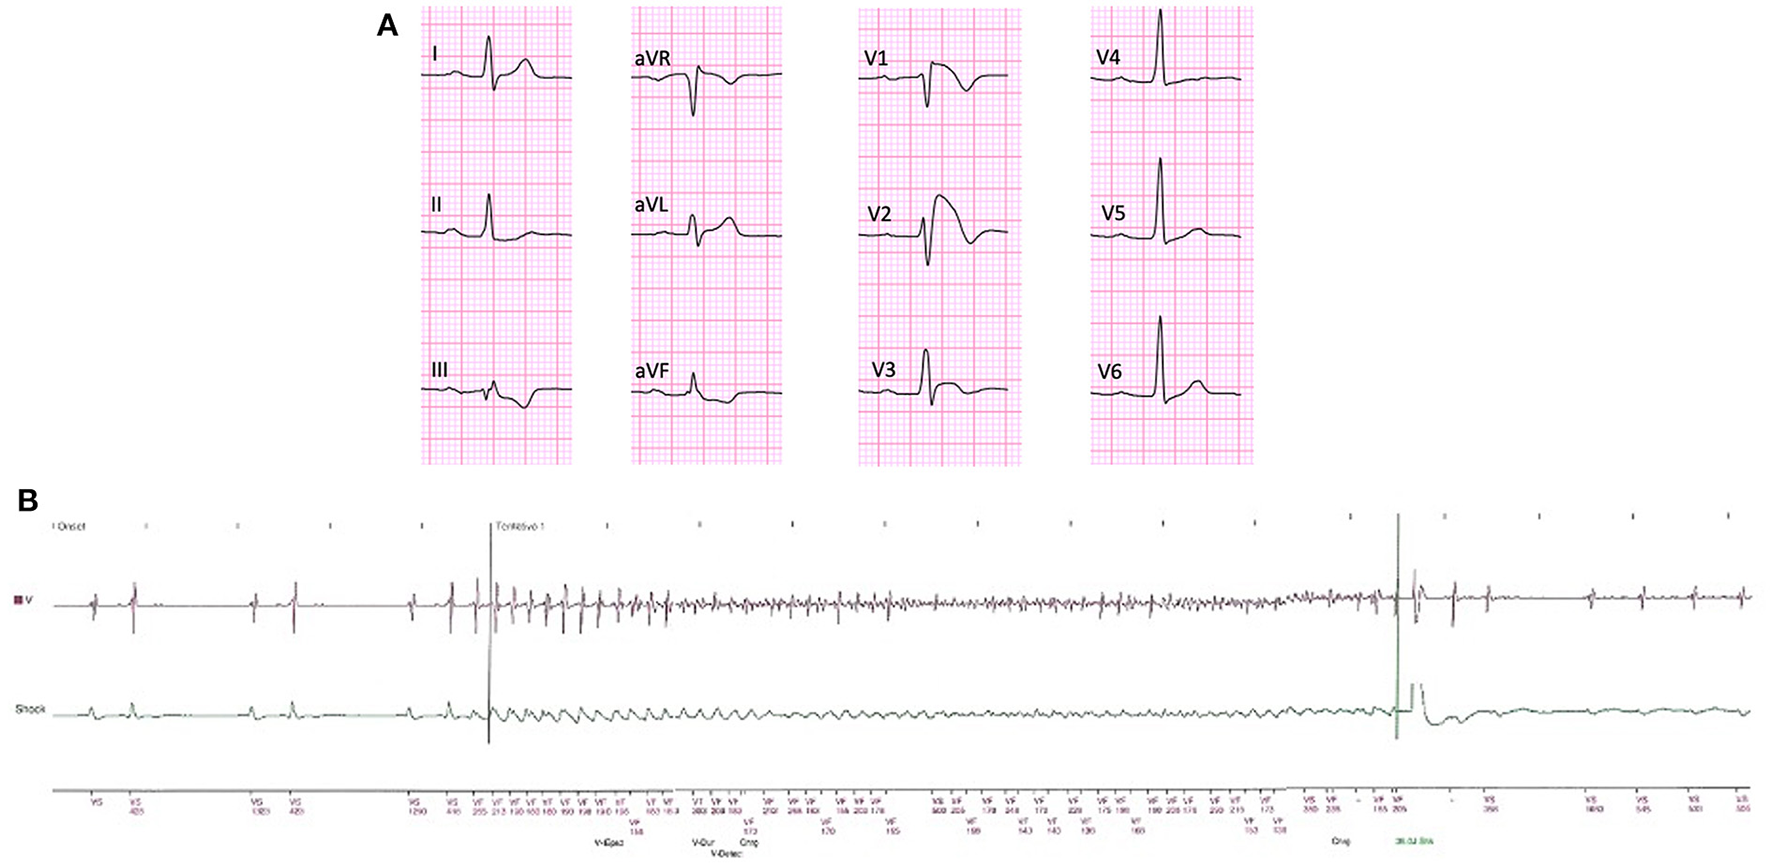

Figure 1

Baseline ECG of an asymptomatic BrS patient who experienced VF 4 years and 6 months after generator replacement. Note the presence of first-degree AV block and S-wave in lead I as well as spontaneous “coved type” ECG pattern in leads V1 and V2 (A). Intracardiac electrocardiogram obtained from the transvenous ICD remote monitoring showing the onset of VF, triggered by a premature ventricular contraction and its offset by the ICD shock (B).